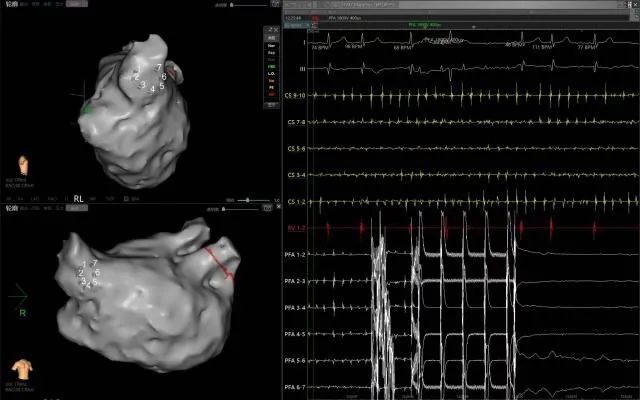

PFA是一種創新且有前景的微創、安全和高效的新興治療方法,通過瞬時的高電壓脈沖電場直接作用于心肌細胞,以不可逆電穿孔機制消融心臟組織,有效的隔絕異常激動及異位傳導路徑,從而恢復正常心律。PFA具有獨特的消融組織選擇性、消融時間極短、無熱損傷炎性水腫和附帶周圍組織損傷并發癥等特點,是現有技術中針對心律失常更理想的消融手段,可大大減少因傳統消融存在手術并發癥風險及消融不足導致房顫復發的風險。與傳統的射頻導管消融或冷凍球囊消融相比,脈沖電場消融手術具有更加安全、消融效率高、并發癥少等諸多優點,徹底改變了房顫治療的格局,為房顫患者帶來更好的治療方案,帶來更多治愈的希望。

此次手術患者均為持續性房顫患者,由延安大學咸陽醫院吳棟梁院長、心律失常專家劉雄濤副院長帶領介入團隊開展,安全高效、圓滿完成手術,手術過程患者全程清醒,術中自訴感覺良好,無痛苦感受。術后患者的心律恢復并維持了竇律,目前恢復情況良好,無任何并發癥出現。